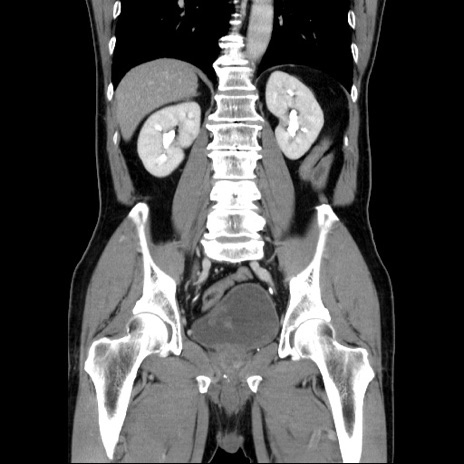

症例34(冠状断像)

【症例】60歳代 男性

【主訴】右鼠径部膨隆

【現病歴】1年程前より右鼠径部膨隆あり。自己にて還納可能だったため放置していた。3時間前より右鼠径部の脱出を認め、還納困難となり受診。

【既往歴】高血圧

【身体所見】右鼠径部に小児頭大の膨隆あり。弾性硬であり、用手還納は困難。左鼠径部にも膨隆を認める。脱出はなし。

【データ】WBC 15500、CRP 測定なし